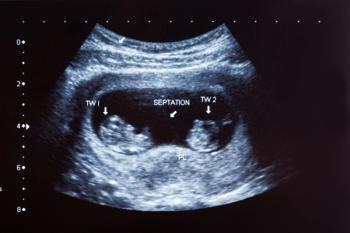

Learn how a mandatory elective single-embryo transfer policy in publicly funded in vitro fertilization programs significantly decreases multifetal pregnancy rates, offering insights into mitigating risks in assisted reproduction.